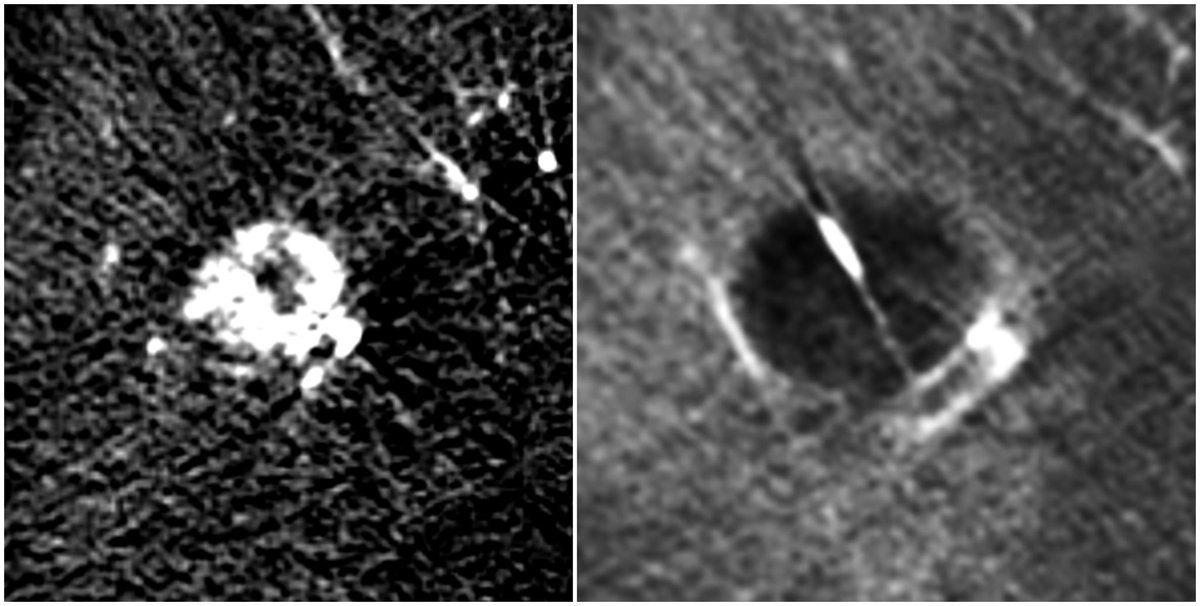

Segment 8 hepatocellular carcinoma obliterated with ultrasound and arteriography-guided percutaneous ethanol ablation using the ProFusion Therapeutic Needle by

#IRAD#Johnson#Khorsand@davidsshin@UW@SIRRFS@SIR_ECS@medravipic.twitter.com/CyrazYiBaU